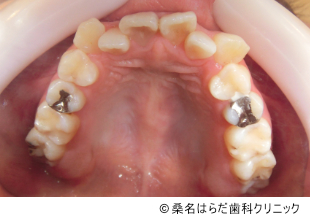

【症例4】マウスピース矯正を用いた叢生および八重歯の矯正治療

- 治療前

- 治療後

- 治療名

- マウスピース矯正を用いた叢生および八重歯の矯正治療

- 費用

- 498,000円(税込)

- 期間

- 1年9ヶ月

患者様の症状

-

歯磨きのしづらさや歯周病の悩みから、歯並びを気にされて来院されました。

治療法

患者様の治療負担を減らすため、患者様と相談のうえでマウスピース矯正を選択しました。

3D光学スキャナを用いてデータをとり、治療計画と装着方法をお伝えして治療を進めました。 -

治療結果

目立っていた八重歯も生えそろい、審美的・健康的な歯並びに変わりました。

※治療結果は個人差があります。